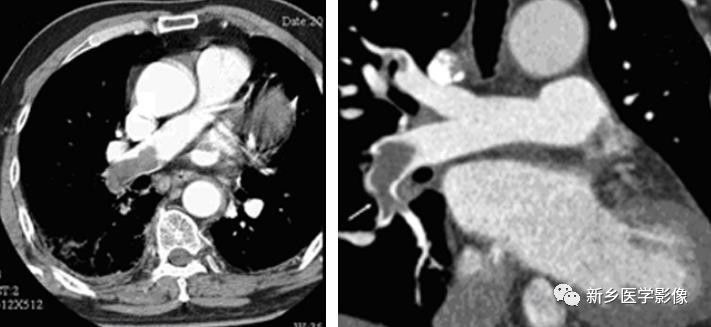

急性肺动脉栓塞CT图像

a. CT横断面示右肺动脉内较大充盈缺损  b. MPR示右肺动脉急性栓塞